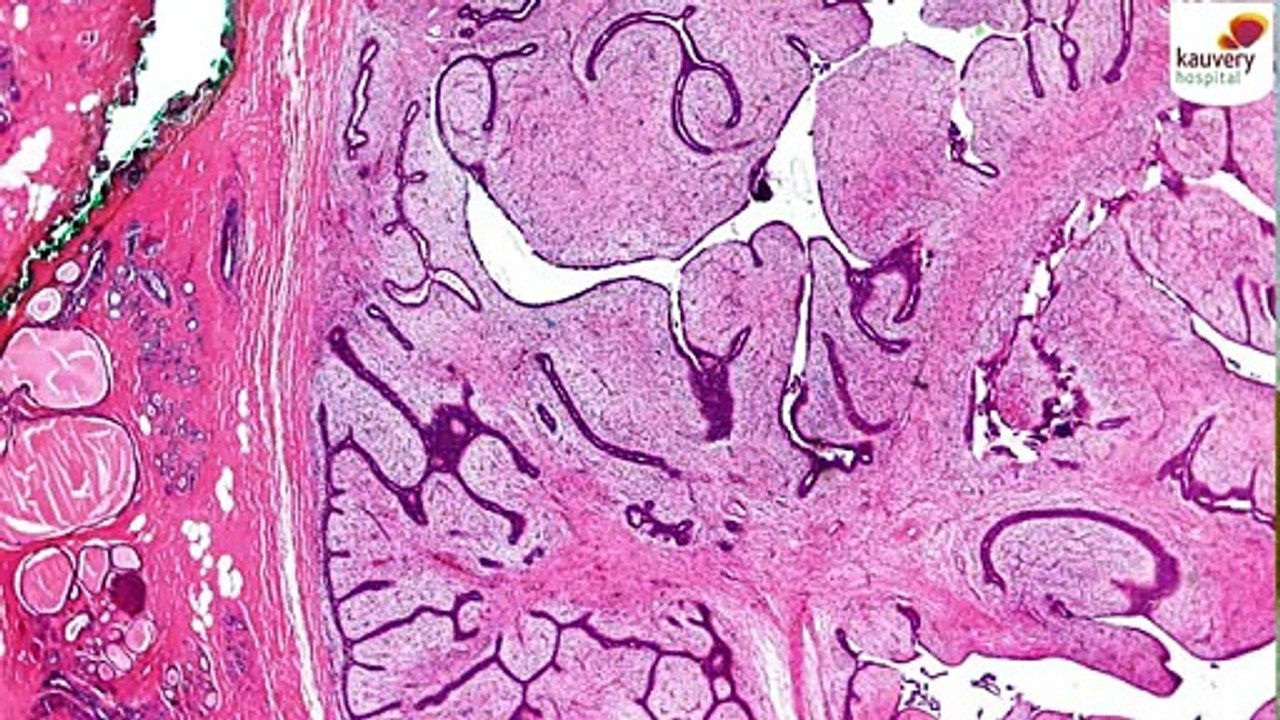

Phyllodes Tumor - Causes, Symptoms & Treatment 2:05

Phyllodes Tumor - Causes, Symptoms & Treatment

Kauvery Hospital 7 views